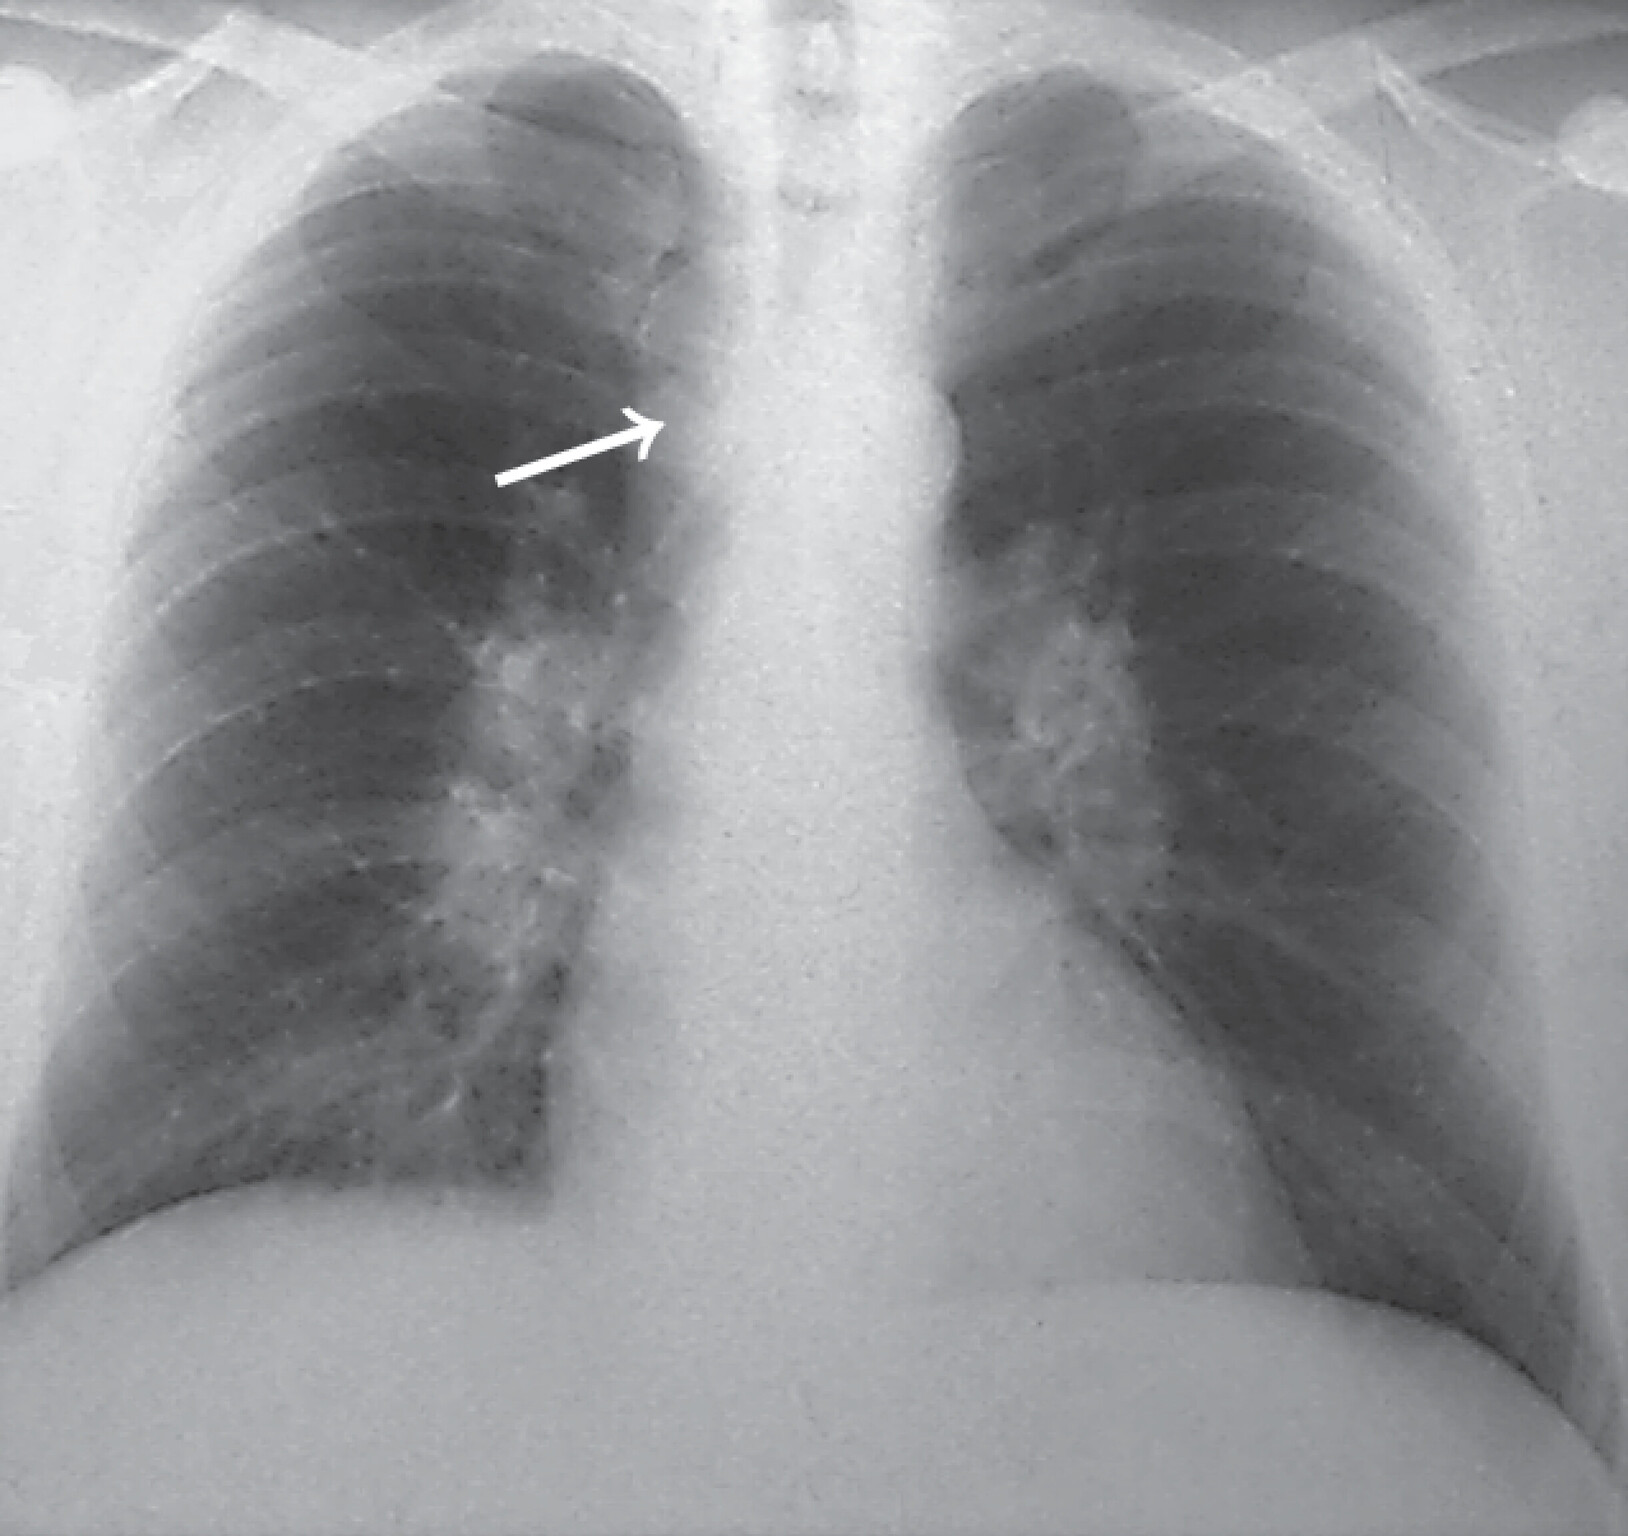

Besteht der Verdacht einer Sarkoidose, sollte eine Röntgen-Thorax-Übersicht durchgeführt werden. Die Lungensarkoidose kann nach dem Röntgen-Thorax-Befund in vier Röntgentypen eingeteilt werden (Abb. 27.8):

- Typ I: beidseitige Hilusadenopathie ohne pulmonale Beteiligungen

- Typ II: beidseitige Hilusadenopathie mit pulmonalen Beteiligungen

- Typ III: pulmonale Beteiligungen ohne Hilusadenopathie

- Typ IV: Zeichen der Lungenfibrose.

Abb. 27.8 Sarkoidose

a Akute Sarkoidose Röntgentyp I. 38-jähriger Mann mit Reizhusten und beidseitiger Sprunggelenksarthritis. Röntgenologisch beidseitige Hiluslymphome, mäßige Verbreiterung des Mediastinums im rechten Tracheobronchialwinkel nach rechts durch Mediastinallymphome (→). Rückbildung der Gelenkbeschwerden nach 2-wöchiger Diclofenac-Therapie.